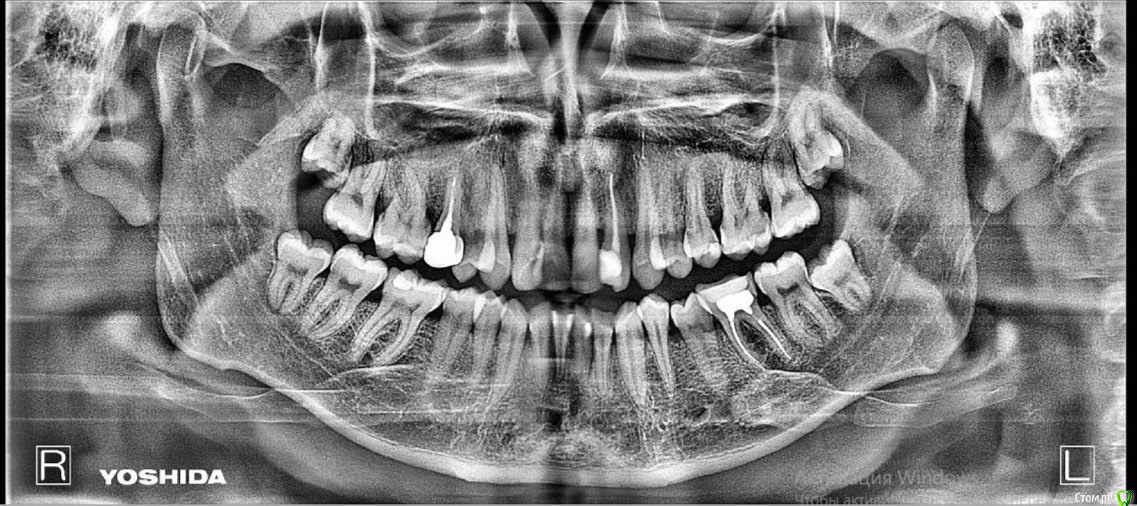

Состояние костной ткани, пародонтит средней степени?

Скажите пожалуйста, при таком состоянии костной ткани/десны возможно лечение с БС?

И какой план лечения/подготовки к брекетам подскажите?

Если у Вас есть парадонтит, то его нужно пролечить. Желательно хирургическим путём.

Признаки парадонтита есть на снимке, но диагноз можно поставить и назначить соответствующее лечение можно только после осмотра полости рта.

Ортодонтическое лечение однозначно можно начинать только после полной санации. В том числе и парадонтологической.